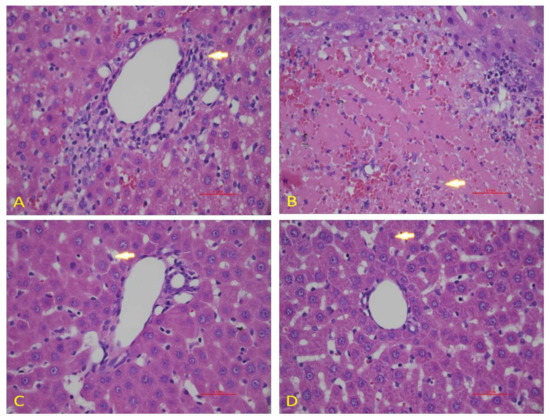

3.5. Effect of Diosmin against DOX-Induced Hepatic Histological Alterations

To confirm the data obtained in our biochemical studies, we evaluated the histological architecture of hepatic tissues after exposure to DOX. We observed a normal hepatic architecture in control animals (Figure 7A). However, DOX exposure caused significant damage in hepatic cells, as shown by the induction of hepatocytes necrosis with marked neutrophilic infiltration (Figure 7B). Nevertheless, diosmin pretreatment showed the presence of a control vein with surrounding normal hepatocytes. However, few residual necrotic hepatocytes were observed in a dose-dependent manner (Figure 7C,D).

Figure 7.

Effects of diosmin pretreatment on light micrographs of the H & E stain liver tissues of 0.1 mm. (A) The normal tissue of the liver. (B) Irregular architecture of liver tissues caused by Dox administration appeared, as indicated by arrows. (C,D) Diosmin pre-treatment reduced harmful effects of Dox in cytoplasmic vacuoles, necrotic hepatocytes, and vascular congestion at both doses.

DOX treatment inhibited PI3K/AKT pathway, as reported in previous findings []. Indeed, the stimulatory action of the PI3K/AKT pathway is crucial for oxidation-mediated cell resistance and apoptosis []. Our results demonstrated the link between the activated form of p-AKT and Bcl-2 up-regulation and subsequently downregulation of Bax expression. A previous study supported the action of p38 mitogen-activated protein kinase (MAPK) in DOX-induced toxicity []. p38 MAPK is a member of the MAPK superfamily composed of four different isoforms: p38α, p38β, p38γ, and p38δ. It has been shown that activation of p38 MAPK is implicated in DOX-triggered apoptosis. In this study, we showed that activation of p-p38 MAPK is a potent enhancer of ROS. In the current study, we showed that diosmin may reverse such enhanced levels of ROS against DOX insult, in line with previous work []. NF-κB is a nuclear transcription factor that plays a pivotal role in the pathophysiology of drug-induced hepatotoxicity []. In its inactive stage, it is more capable of making complexes with its inhibitors, IKα and IKβ. Upon activation, IKα or IKβ promotes phosphorylation of IKβ due to an insult or oxidative stress, leading to the release of NF-κB, enabling its translocation into the nucleus. Our results demonstrated significant activation of NF-κB in response to DOX administration, in accordance with previous findings []. Diosmin pretreatment, however, significantly inhibited the NF-κB- p65 activation cascade. These findings are also consistent with previous reports supporting the capability of a natural compound to hinder NF-κB activation []. Inflammation is a key player in the Dox-induced hepatotoxicity []. In the current study, we examined the genes involved in inflammation, such as TNF-α, IL-1β, IL-6, and iNOS. We found that Dox treatment showed upregulated expression of these genes. Nevertheless, these alterations in gene expression of TNF-α, IL-1β, IL-6, and iNOS were mitigated by diosmin treatment in a dose-dependent manner. These findings were in accordance with previously reported studies [,]. Furthermore, histological evaluation observed in DOX-treated rats revealed marked alterations in liver tissues, such as extensive hepatocytes necrosis with marked neutrophilic infiltration []. Alternatively, pretreatment with diosmin attenuated hepatic necrosis, neutrophilic infiltration, and other dysfunctions, in line with the previously published report [].